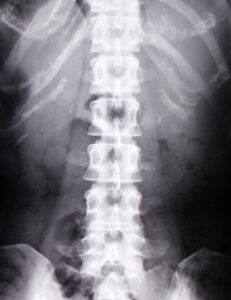

レントゲン検査

主に背骨のX線写真を撮り、骨折や変形の有無、骨がスカスカになっていないかなどを確認します。

骨粗しょう症と他の病気を区別するためにも必要な検査です。